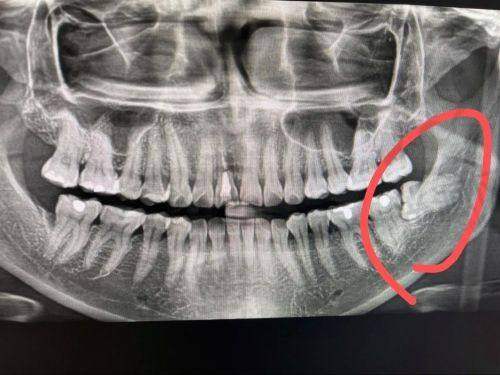

智齿拔牙后窟窿恢复图,智齿拔牙后恢复过程与图片解析,7天到30天牙洞愈合状态详解

智齿拔牙是许多人在成长过程中的一道难关,而了解智齿拔牙后窟窿修复图,可以帮助您更好地应对这一过程。智齿的生长常常伴随着疼痛和不适,尤其是当它们位置不正或受阻生长时,拔除智齿成为了必要的选择。 在拔牙后的修复过程中,患者往往会关心拔牙后的伤口愈合情况,以及正常修复的标准。本文将详细介绍拔智齿后的伤口愈合情况,通过智齿拔牙后窟窿修复图,帮助您了解拔牙后7天、14天、30天的伤口状态和修复进程。并且,我们还将结合医学数据和实际实例,为您提供关于拔智齿后修复的科学认识和行动指南。通过对这些信息的深入理解,您将能更有信心地渡过拔牙后的修复阶段。

在智齿拔牙后,伤口的愈合是每位患者更为关心的事情之一。智齿拔牙后窟窿修复图能够直观展示拔牙后伤口在不同时间阶段的愈合过程,帮助患者更清晰地了解自己的修复情况。研究显示,在拔牙的后的第一个星期,伤口的自我愈合已开始慢慢展现,通常在这一阶段患者会感到疼痛和肿胀,而这也是完全正常的。

通过观察智齿拔牙后窟窿修复图,患者可以了解到,伤口周围组织的再生与愈合过程是一个逐步的过程。在拔牙后的7天内,伤口周围的组织会开始形成一种叫做肉芽组织的物质,这是愈合过程中非常重要的一步。